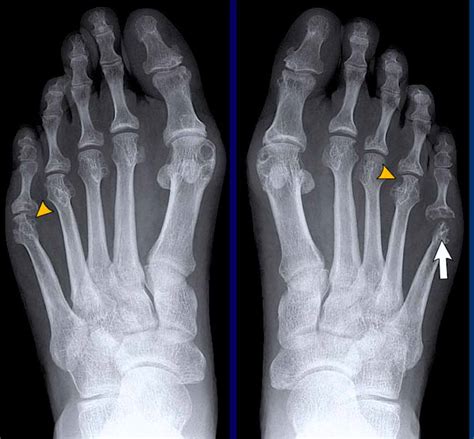

A Lateral Foot X Ray is a type of radiographic imaging that captures a side view of the foot. This view is essential for evaluating the alignment and integrity of the bones, joints, and soft tissues in the foot. Unlike an anteroposterior (AP) view, which provides a front-to-back image, a lateral view offers a different perspective that can reveal issues not visible in other projections.

Common Findings in a Lateral Foot X Ray

A lateral foot X ray can reveal a variety of conditions and abnormalities. Some of the most common findings include:

• Fractures: Fractures of the calcaneus, metatarsals, or other foot bones can be clearly seen in a lateral view.

• Arthritis: Joint space narrowing, bone spurs, and other signs of arthritis can be identified.

• Deformities: Conditions like flatfoot, high arches, or bunions can be evaluated.

• Foreign Bodies: Objects embedded in the foot, such as glass or metal, can be detected.

• Soft Tissue Abnormalities: Swelling, cysts, or other soft tissue issues can sometimes be seen.

• Comparison Views: Sometimes, comparing the lateral view with other projections (e.g., AP view) can provide a more comprehensive assessment.